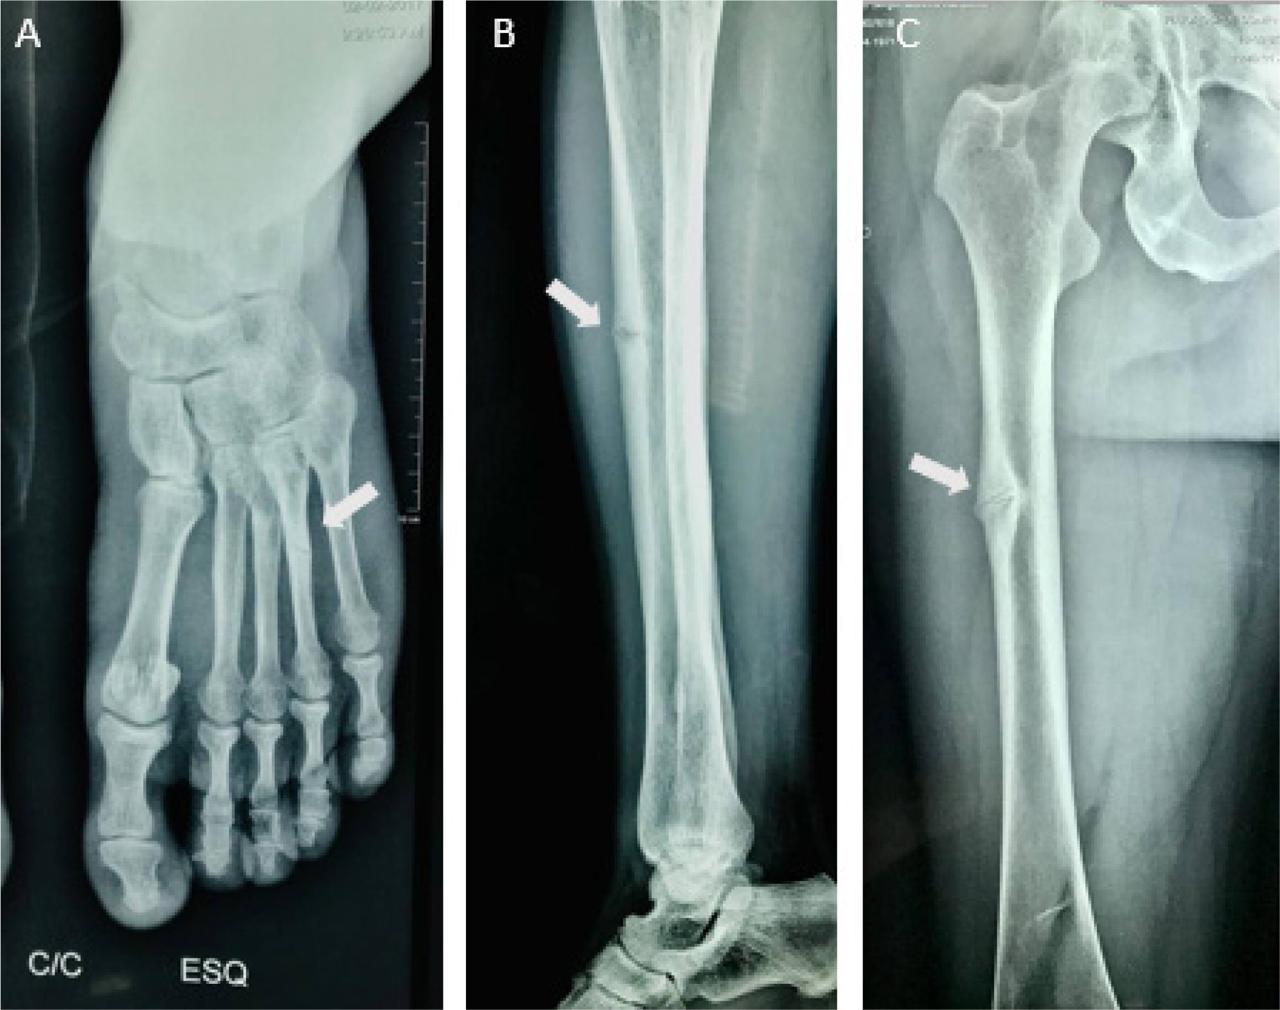

В ЧОДКБ поступила 15-летня девочка с жалобами на сильные боли в мышцах, слабость и ухудшение памяти. Из-за этого подросток перестал ходить в колледж и общаться с друзьями.

Ей даже успели сделать операцию по исправлению деформированной стопы. Но после хирургического вмешательства начались осложнения. Не помогли консультации и у московских медиков. Девочку даже начали подозревать в симуляции.

Неизвестно чем бы все закончилось, если бы пациентка не челябинский врач-генетик. Выяснилось, что проблема не в костях, а в редком генетическом заболевании. После постановки верного диагноза и лечения, организм начал восстанавливаться. Девушка снова вернулась к учебе в колледже и друзьям.